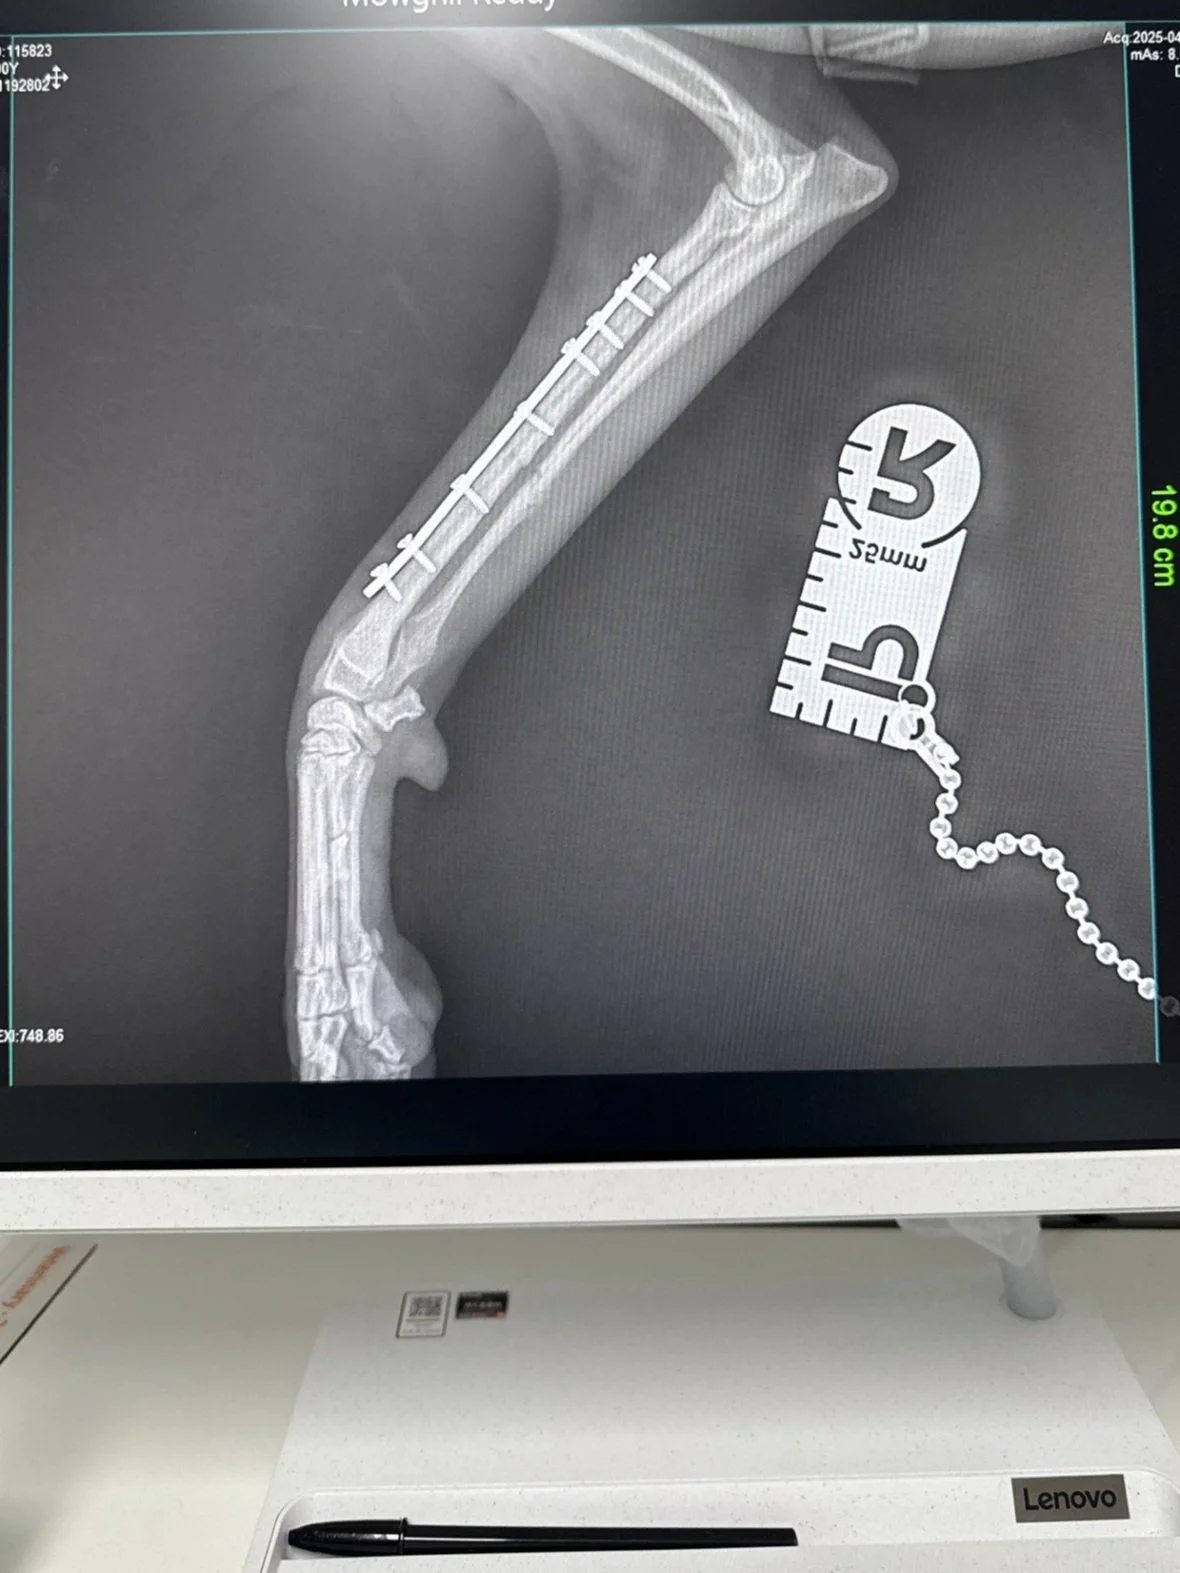

Orthopaedic Surgery Techniques We Offer

We perform a wide range of orthopaedic surgical procedures, suited to the type and severity of your pet’s fracture.

• Titanium and stainless-steel locking and compression plates

Advanced Diagnostics for Precise Care

We use digital radiography (X-rays) and CT scanning to accurately diagnose fractures and plan the most effective orthopaedic surgery.